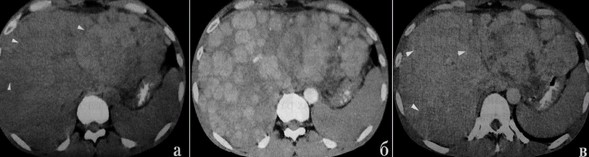

Цирроз печени на КТ с контрастом

Примеры изменений паренхимы железы в зависимости от типа процесса

КТ признаки цирроза печени

Норма и патология

Критерием для постановки диагноза рассматривают:

- увеличение/уменьшение размеров печени на КТ;

- бугристые контуры органа (при крупноузловой форме цирроза);

- визуализацию расширенных множественных септ — фиброзных перегородок;

- спленомегалию;

- варикозное расширение вен в области интереса, формирование коллатерального кровообращения, артерио-портальных и порто-венозных шунтов;

- фиброз, жировые изменения;

- сморщивание правой доли и гипертрофия левой — симптом “целующихся печени и селезенки” типичен для поздней стадии.

Дифференциальный ряд включает заболевания, имеющие на КТ схожие с циррозом печени признаки:

- метастатическое поражение;

- лимфопролиферативные процессы;

- саркоидоз;

- гепатоцеллюлярную карциному;

- узловую регенераторную гиперплазию.

Выраженная адвентициальная сеть без возможности различить стенку пищевода

Расширенные сосуды дифференцируют с увеличенными лимфоузлами, что возможно при выполнении многоплоскостных реконструкций изображений и использования ангиорежимов.